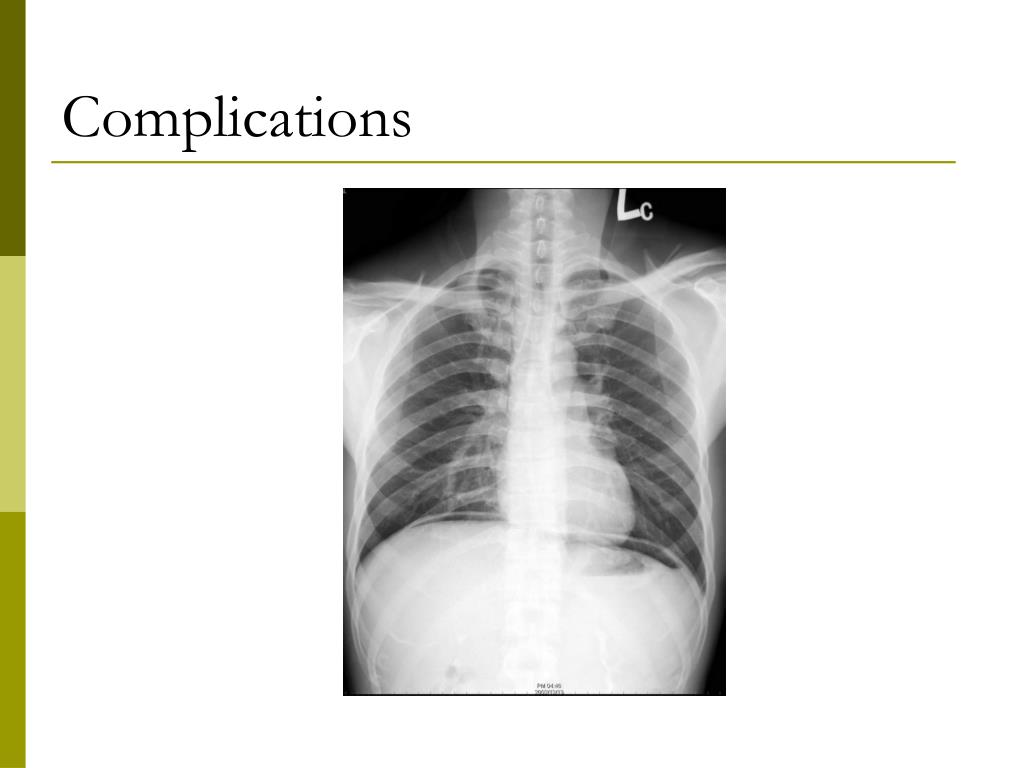

29. Complications

30. Serious Complications • BC, Alberta, Ontario, Nova Scotia • Population 50-75 yr: 4.6 million • Persons 50-75 yrs who underwent outpatient colonoscopy between 4/1/2002 and 3/31/2003 • Outcome: Bleeding and perforation requiring admission within 30 days of colonoscopy Rabeneck et al. Gastroenterology 2008;135:1899-1906

31. Results • 97,091 persons had an outpatient colonoscopy from 4/1/2002 to 3/31/2003 • Bleeding 1.64/1000 • Perforation 0.85/1000 • Death 0.074/1000 or 1/14,000 • Risk factors: increased age, male sex, polypectomy, volume < 283/yr